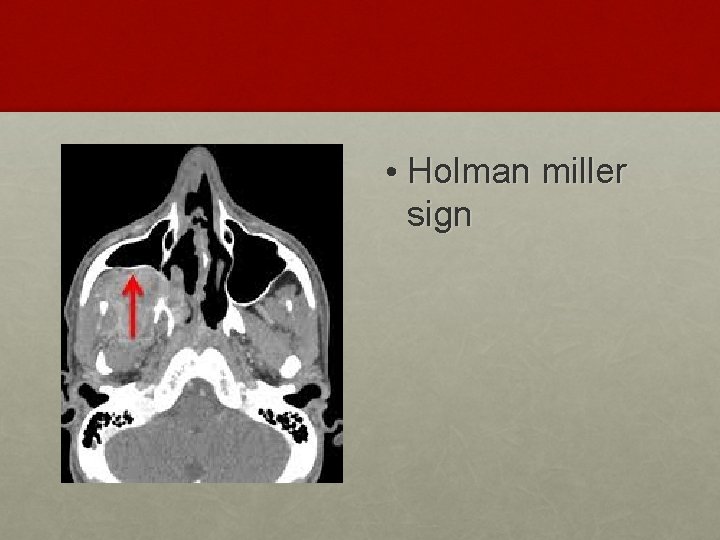

INVESTIGATION: • Contrast enhanced CT scan of nose and PNS • Holman Miller sign/ Antral sign • MRI – soft tissue extent

• Holman miller sign